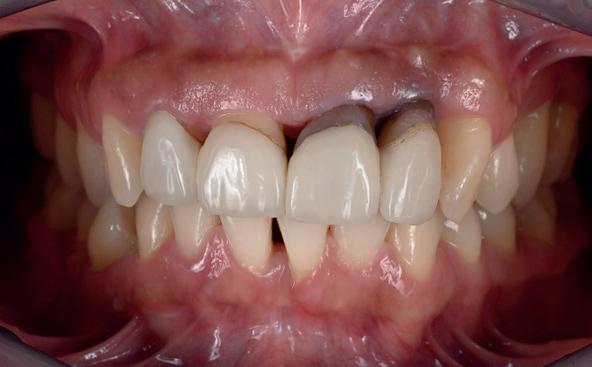

3. Lichtfoto intake

4. Lichtfoto na infectie controle